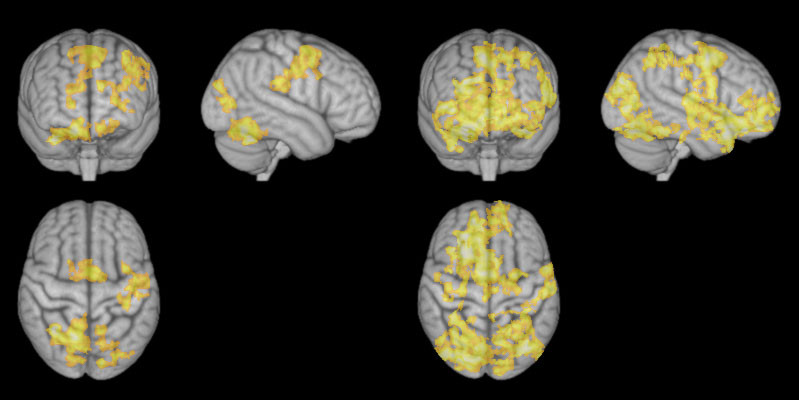

Οι ερευνητές παρακολούθησαν την εγκεφαλική δραστηριότητα δεκατεσσάρων ανθρώπων, ενώ εξασκούσαν – σε διαφορετικές στιγμές – τις δυο μεθόδους διαλογισμού. Η δραστηριότητα του εγκεφάλου είναι μεγαλύτερη στο κέντρο των συναισθημάτων και των σκέψεων όταν διαλογίζεται πιο ελεύθερα (φωτογραφίες δεξιά)

Η δραστηριότητα του εγκεφάλου είναι μεγαλύτερη στο κέντρο των συναισθημάτων και των σκέψεων όταν διαλογίζεται πιο ελεύθερα (φωτογραφίες δεξιά)

Το ενδιαφέρον και μάλλον αναπάντεχο εύρημά τους, είναι ότι όταν οι συμμετέχοντες έκαναν τον «ελεύθερο μη κατευθυνόμενο διαλογισμό, παρουσιαζόταν μεγαλύτερη δραστηριότητα στην περιοχή του εγκεφάλου που σχετίζεται με την επεξεργασία των σκέψεων και των συναισθημάτων. Από την άλλη μεριά, όταν έκαναν την πιο εστιασμένη τεχνική διαλογισμού η δραστηριότητα στην ίδια περιοχή του εγκεφάλου ήταν παρόμοια με εκείνη που εκδηλώνεται σε φάση ξεκούρασης και ανάπαυσης.